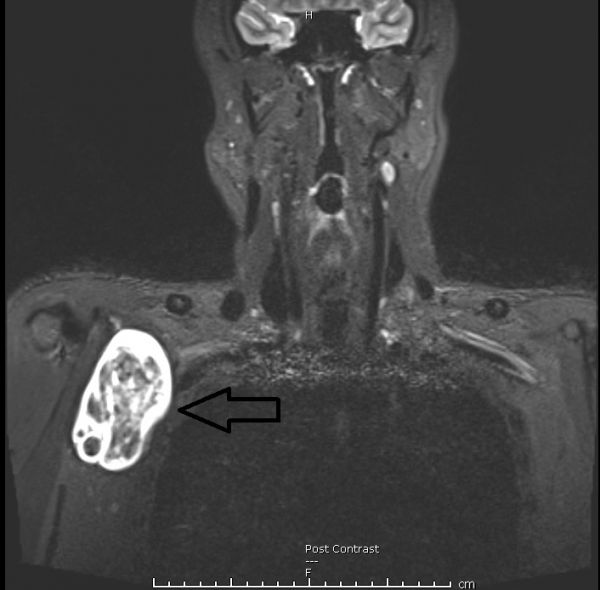

我给阿虎体检时,他的四肢感官、力度和反应能力全都达标,接下来做磁力共振扫描,右腋下那颗7×8公分的神经鞘瘤才无所遁形。神经鞘是覆盖神经的组织,神经鞘瘤一般属良性肿瘤,可以手术切除,复发的几率亦很小。